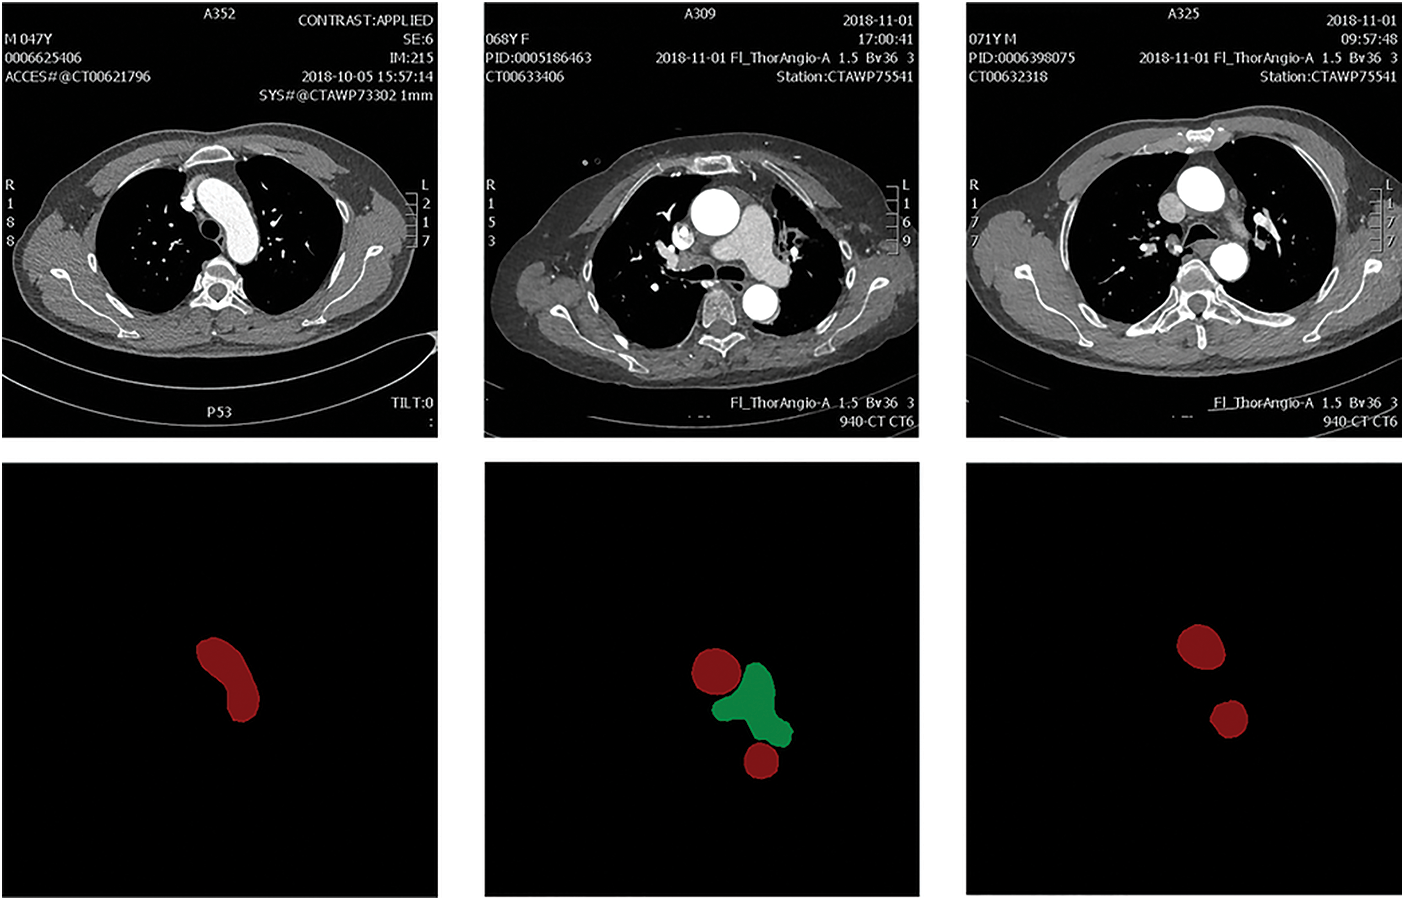

The dataset used in this work is the dataset of arterial angiography, which consists of 2608 images in total. The mask label is completed under the guidance of medical experts. The dataset images mainly include the aorta (AA) and pulmonary artery (PA), and the image size is 512 × 512. The image and annotation label visualization results of the constructed arterial dataset are shown in Fig. 4. The data image at the top and the corresponding labels at the bottom. The red area in the label map is AA and the green area is PA.

Figure 4: The constructed arterial dataset